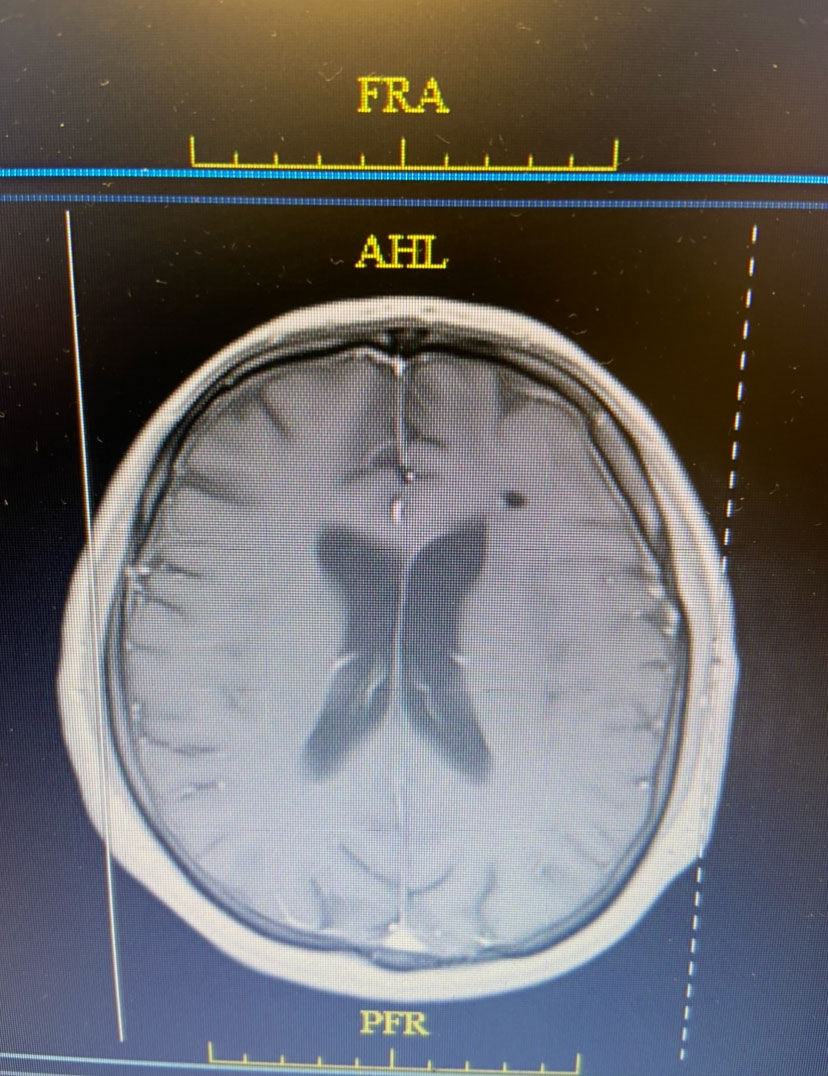

Postoperatively, the patient was started on broad spectrum IV antibiotics, under the supervision of an Infectious Disease consult. Clinically, the patient gradually recovered. Within weeks, the patient had fully recovered and was neurologically intact. Gram stains were suspicious for the presence of bacteria (encapsulated cocci). Cultures never grew out any organisms. The patient was treated with several weeks of broad spectrum IV antibiotics. The patient made a full recovery. (Image 3, axial post contrast MRI from 3 months post-op shows resolution of brain abscess and surrounding edema. )

Axial post contrast MRI from 3 months post-op shows resolution of brain abscess and surrounding edema

Image 3: Axial post contrast MRI from 3 months post-op shows resolution of brain abscess and surrounding edema.